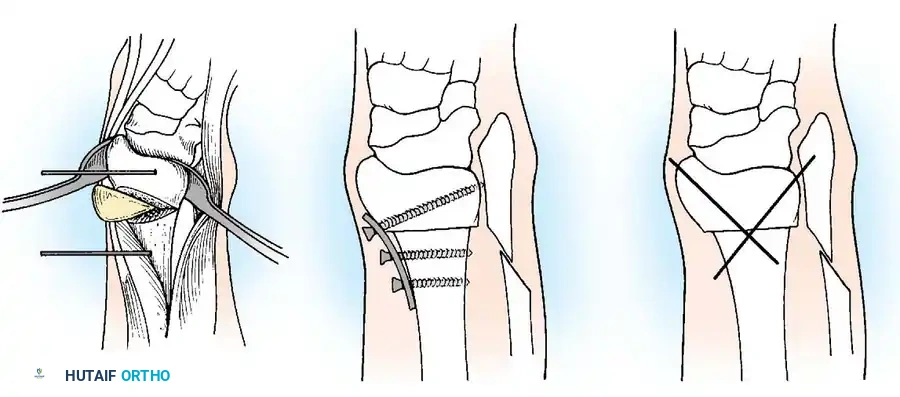

When conservative measures fail, surgical intervention is required:

1. Comprehensive Posteromedial Release (PMR): Involves lengthening of the Achilles, posterior tibialis, FDL, and FHL, along with extensive capsulotomies of the ankle, subtalar, and talonavicular joints.